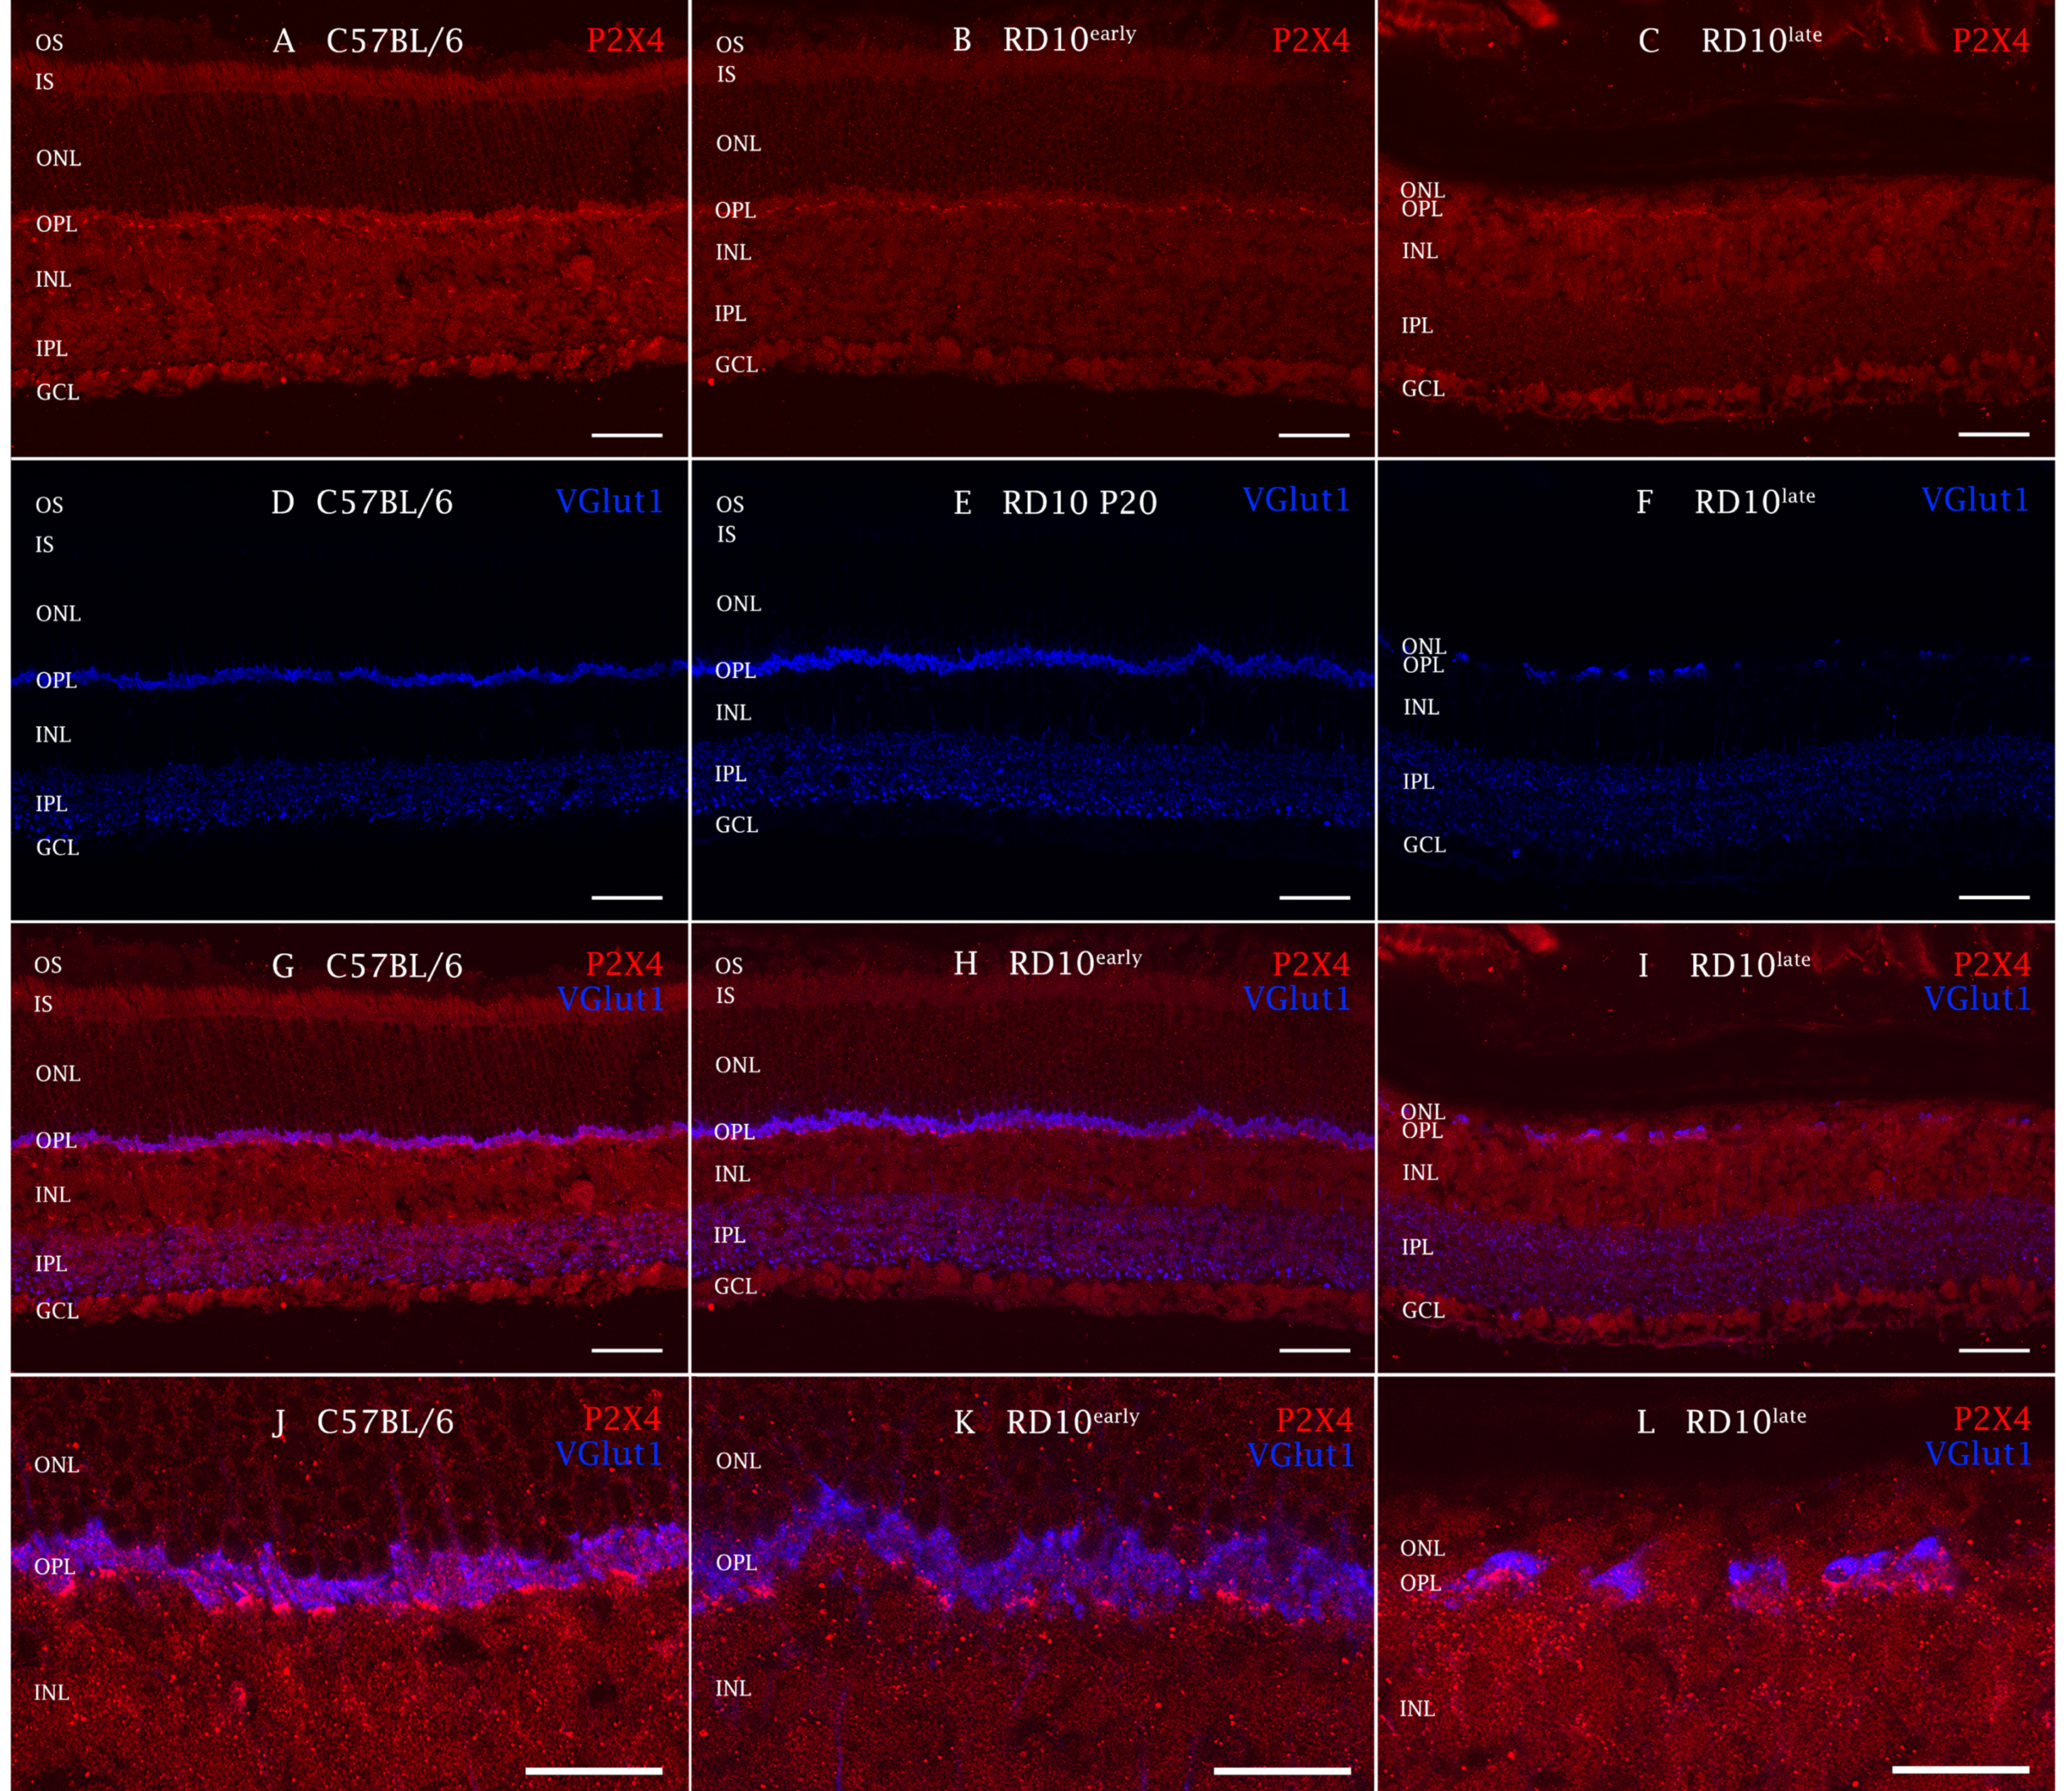

2.3. P2X4R Expression in rd10 Mice